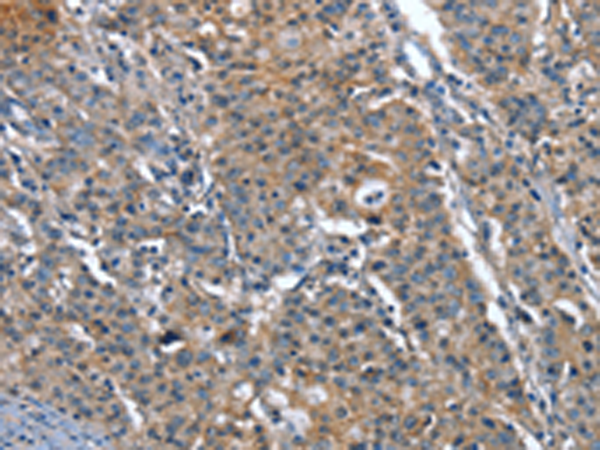

分类: 科研抗体货号: P04694别名: BSP1; JV41; BSP-1; JV4-1; MADH1; MADR1应用: IHC反应种属: Human, Mouse, Rat